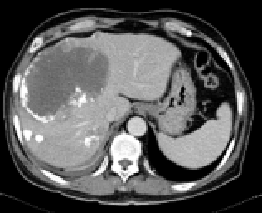

2014-06-04CT:

影像学检查:

2014-08-25CT: